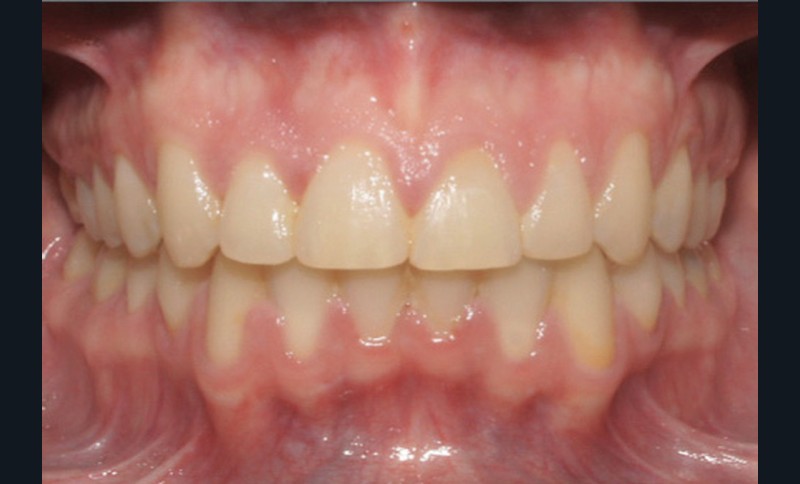

Discussion (fig. 4 à 7)

Le traitement a duré vingt-quatre mois. Le décalage de classe II complet à droite a nécessité une mécanique importante impliquant une bonne coopération du patient ainsi qu’un contrôle rigoureux des effets parasites. Les documents de fin de traitement nous montrent une normalisation des rapports incisifs. La correction de la classe II a entraîné une vestibulo-version de l’incisive mandibulaire qui reste néanmoins acceptable, et qui participe à la fermeture de l’angle interincisif, recherchée dans le traitement des classes II division 2. Les fonctions ont été rééduquées. Sur le plan esthétique, les améloplasties réalisées sur les bords libres de 12 à 22 ont permis d’effacer les séquelles de la supraclusion et participent à l’harmonisation du sourire.